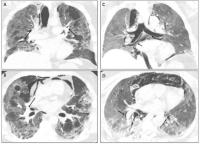

The Macklin effect seen on CT. Arrows point to areas of accumulation of air along the peripheral bronchi or pulmonary vascular sheath.

Senior author and cardiothoracic imaging fellow Kathleen M. Capaccione, MD, PhD, and her colleagues in the Division of Cardiothoracic Imaging, evaluated CT scans of patients who were critically ill, intubated, and COVID-19 positive. 10 patients exhibited the Macklin effect, and nine of those patients developed barotrauma.